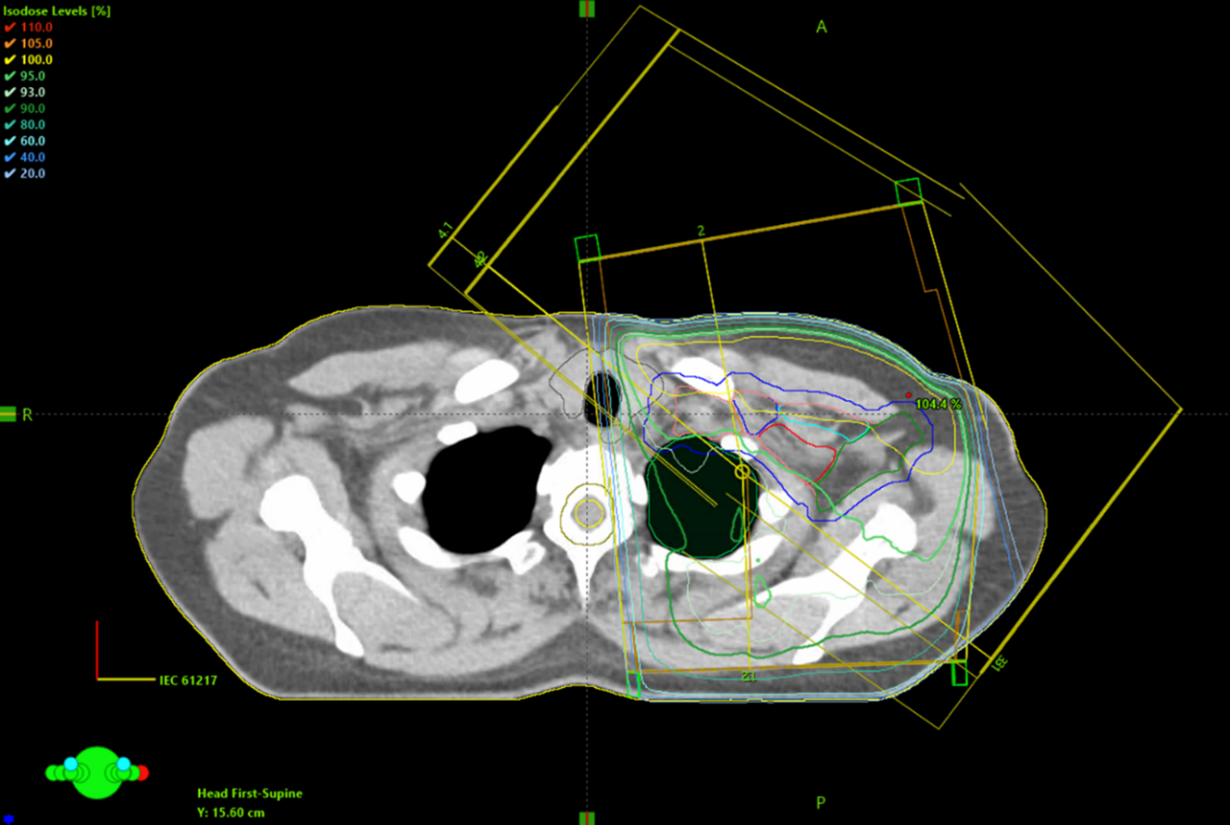

Figur 6. Exempel på dosplan med tangentiella strålfält.

Figur 8. Exempel som visar placeringen av isocenter och CT-snittet för övergången mellan tangentiella strålfält över brösttarget och strålfälten över körteltarget.

Figur 10. Exempel på dosplan med strålfält över bröstkörtelvolymen.